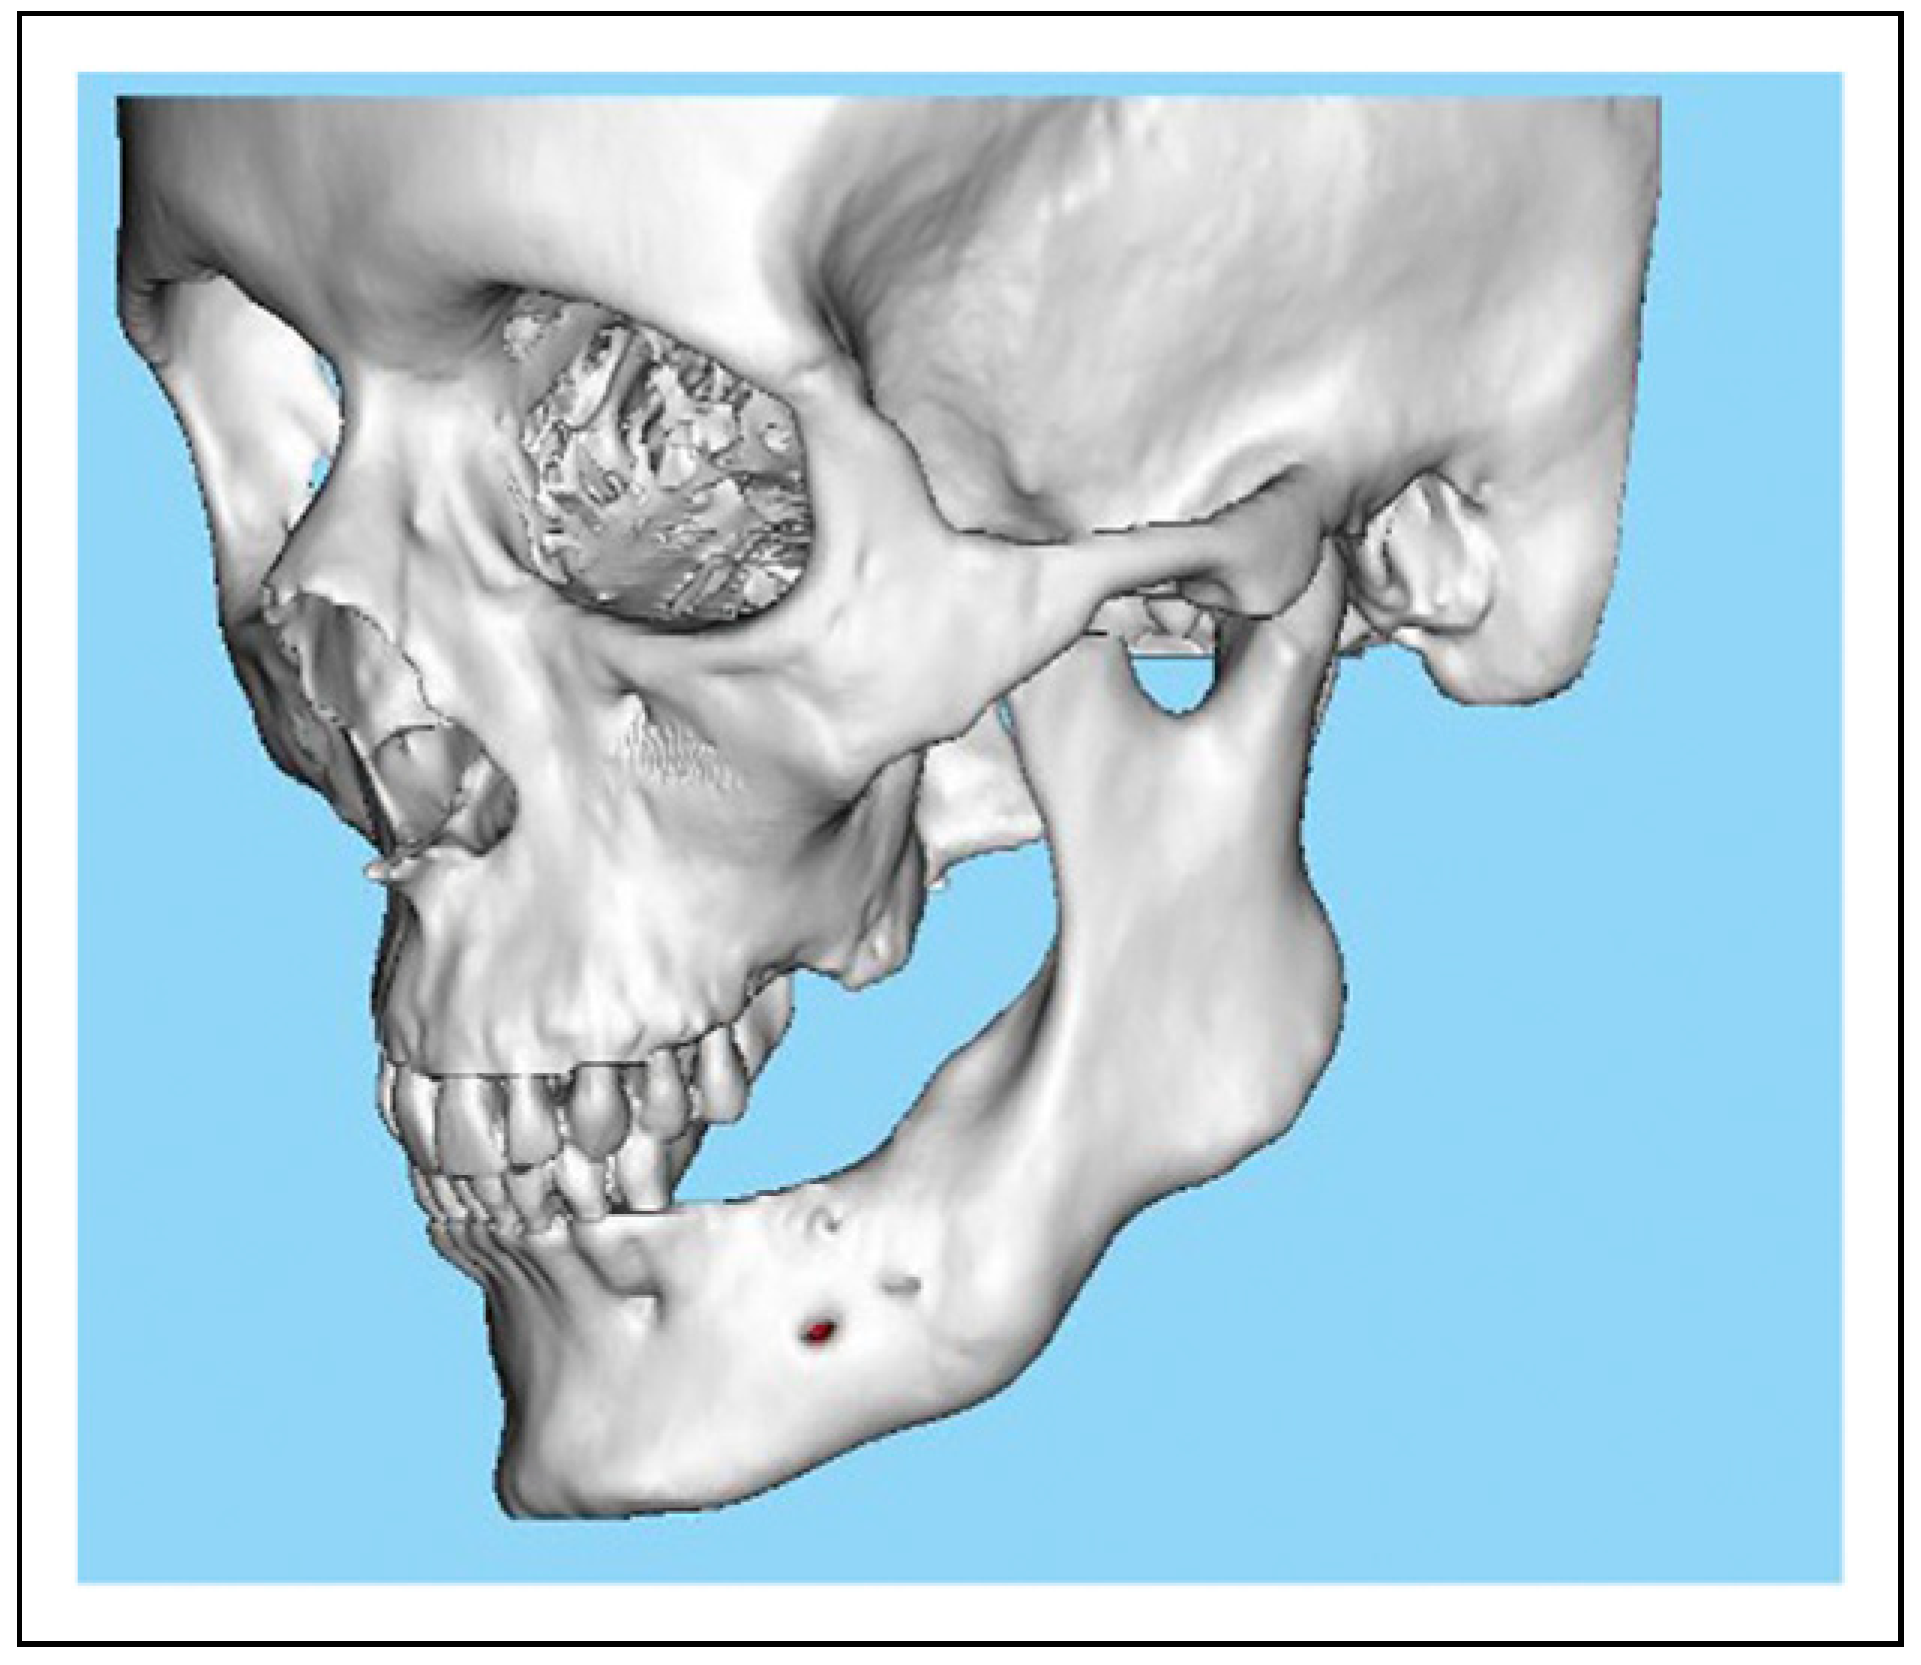

Bilateral TMJ Replacement With Complete Replacement of the Mandible, Patient 8